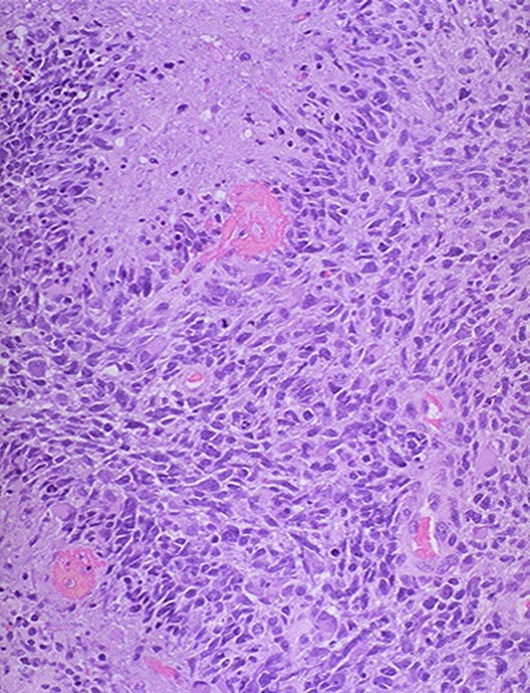

Lots of hemorrhaging, weak blood vessels, and necrosis growing fast

GBM

pleomorphic astrocytes

mitotic activity

vascular proliferation here

necrosis

know this picture!

Palisading neoplastic cells surrounding necrosis

GBM grade 4 astrocytoma

Geographic pattern, a perimeter of neoplastic glial cells surrounding necrosis